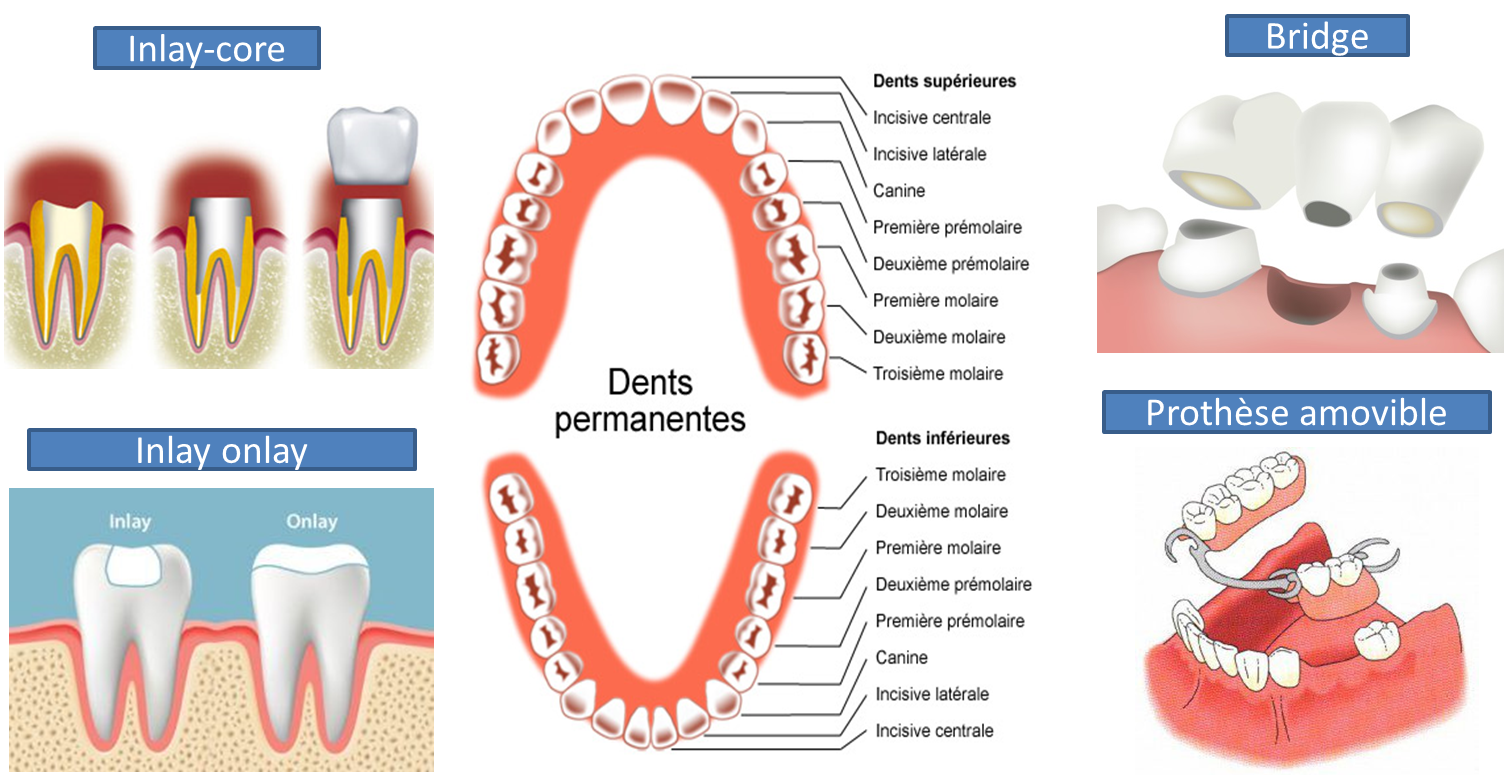

This option allows the patient to enjoy a full set of teeth. The hybrid denture is fixed and does not require removal every day like regular. How fixed hybrid implant restoration is done. Hybrid dentures are dentures that permanently attach to the mouth through the use of dental implants. This option allows the patient to enjoy a full set of teeth. Sue had upper and lower partial dentures for years. Dentures, removable replacements for missing teeth, are available as partial dentures and complete dentures. Snap in dentures, fixed hybrid bridge, and fixed zirconia bridge may need an extra stage. You can compare dentures and implants here. Fixed hybrid dentures is a process of treating severe dental problems, which hare otherwise hard to treat. A bridge is a common dental restoration that can replace one or more missing teeth by literally bridging the gap they left behind. Denture costs vary and most insurance companies can cover the cost of dentures. This is why they are often called hybrids. There are multiple reasons why patients lose their teeth, including gum disease and other dental complications. The hybrids need to be removed and cleaned periodically by your dentist, however the flanges can be trimmed to allow better access for waterpik if you hi, the pictures posted are for 2 different dentures, the above picture is a fixed denture that is fixed directly to the implants/abutments and has no. A hybrid denture prosthesis is the. I have seen two dentists regarding full arch dental implants for my lower jaw. How many teeth they are replacing (full or partial). Over dentures are far better for the lower jaw that they are for the upper jaw. What is the hybrid denture option? A hybrid denture is attached by four or more implants in the jaw, depending on the jawbone size and shape. It gets food caught in it all the time. The result is a new set of teeth that are cosmetic and strong and allow a person the use and. Unlike conventional dentures, immediate dentures are made in advance and can be positioned as soon as the teeth are removed. I just received the permanent hybrid. Dentures, also known as false teeth, are a type of dental prosthesis for people missing one, some, or all of their teeth. Regular hybrid dentures, all on 4. The hybrid fixed dentures are also less expensive than other dental implant options, making them affordable, convenient and functional for our patients. Traditional acrylic w/titanium substructure, smartcomposite hybrid prosthesis, and zir.max.m® a unique approach within the fixed hybrid category of restorations. A fpd may require an anterior cantilever away from the soft tissue in a horizontal and vertical dimension to provide this fixed partial dentures are susceptible to several common problems, including debonding; There are a lot of dental procedures to fix this type of dentures the most common are: